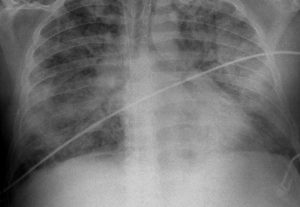

La neumonía es una infección del pulmón que puede ser causada por diferentes gérmenes como bacterias, virus y hongos. Es la infección que con mayor